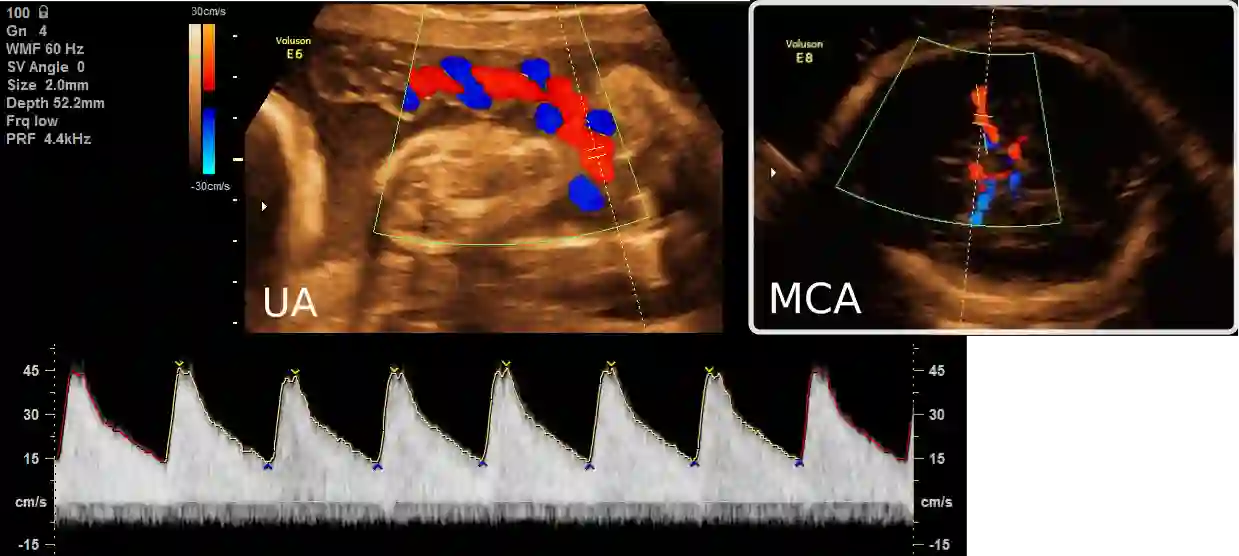

Examination of the umbilical artery with Doppler ultrasonography is performed to investigate blood supply to the fetus through the umbilical cord, which is vital for the monitoring of fetal health. Such examination involves several steps that must be performed correctly: identifying suitable sites on the umbilical artery for the measurement, acquiring the blood flow curve in the form of a Doppler spectrum, and ensuring compliance to a set of quality standards. These steps rely heavily on the operator's skill, and the shortage of experienced sonographers has thus created a demand for machine assistance. In this work, we propose an automatic system to fill the gap. By using a modified Faster R-CNN network, we obtain an algorithm that can suggest locations suitable for Doppler measurement. Meanwhile, we have also developed a method for assessment of the Doppler spectrum's quality. The proposed system is validated on 657 images from a national ultrasound screening database, with results demonstrating its potential as a guidance system.